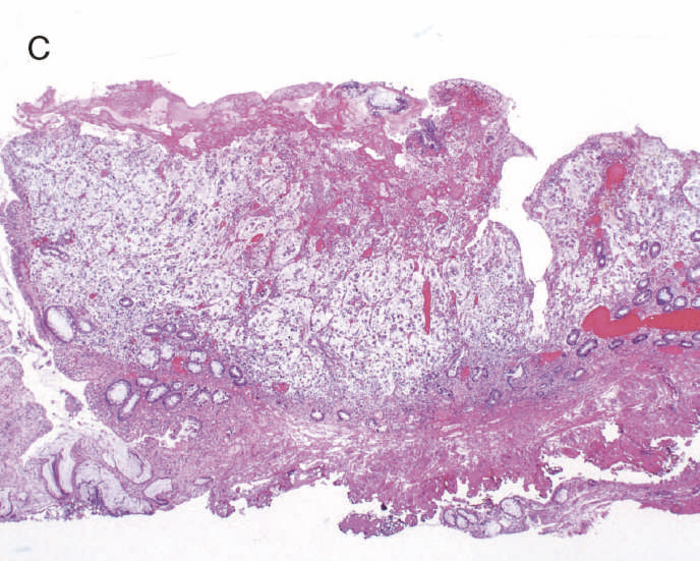

このように多彩な像を呈するdysplasiaでは,特に異型度が低い場合に反応性異型との鑑別にしばしば難渋するが,dystrophic goblet cell,endocrine cell hyperplasia,Paneth細胞化生などの特徴的な上皮細胞分化異常を示す特殊な異型上皮の存在が形態学的な鑑別として有用である。また,dysplasiaでは,腫瘍発生早期の段階よりTP53遺伝子異常が起こることが知られている。したがって,上記の形態学的な異常とともに,免疫染色におけるp53蛋白異常発現の有無が反応性異型や散発性腺腫との鑑別において重要となる(TP53遺伝子変異が見られる際には,免疫染色においてp53蛋白過剰発現あるいは完全欠失を示すことが知られている)。これまでに,一般大腸腺腫・癌ではp53蛋白過剰発現はその異型度に相関するのに対し(腺腫で0.8~3.4%,低異型度癌で35.3%,高異型度癌で71.7%),dysplasiaでは低異型度の段階から高頻度(75%)にp53蛋白過剰発現を呈することが報告されている5)。したがって,特に低異型度腫瘍でp53蛋白異常発現パターンを示す場合はdysplasiaの可能性が高く,反応性異型との鑑別において診断的意義が高い。また,表層分化傾向を示すLGDではp53蛋白の過剰発現がある場合でも表層部ではp53蛋白の発現減弱がしばしば観察されるのに対し(unique basal patternと呼ばれる),HGDでは全層性にp53蛋白過剰発現を示すことが多い。Ki-67(増殖マーカー)染色では,dysplasiaでは細胞増殖帯が粘膜深層~中層に位置するが(bottom-up pattern),散発性腺腫では細胞増殖帯が腺管表層~中層に分布することが知られている(top-down pattern)。これらの免疫染色パターンは,dysplasiaと反応性異型や散発性腺腫との鑑別の際に重要な手がかりとなる(図9,図11)(CQ 12,CQ 13)。

図9 Dysplasiaの代表的な組織像

- LGDの組織像(HE染色):異型腺管では表層への分化傾向が見られる。

- aのp53免疫染色:異型腺管深部側優位にp53蛋白過剰発現が見られる。

- HGDの組織像(HE染色):異型腺管では表層まで核腫大と重積が認められる。

- cのp53免疫染色:異型腺管表層部までp53蛋白の過剰発現が見られる。

図11 LGDと散発性腺腫の代表的な病理組織像と特徴的免疫染色像

表層への分化傾向を示すLGDでは異型腺管深部側優位にp53蛋白過剰発現が見られるのに対し,散発性腺腫ではp53蛋白異常発現は認められない。また,Ki-67(増殖マーカー)染色においては,LGDでは細胞増殖帯が粘膜深層~中層に位置するが(bottom-up pattern),散発性腺腫では細胞増殖帯が腺管表層~中層に分布する(top-down pattern)(CQ 12,CQ 13)。